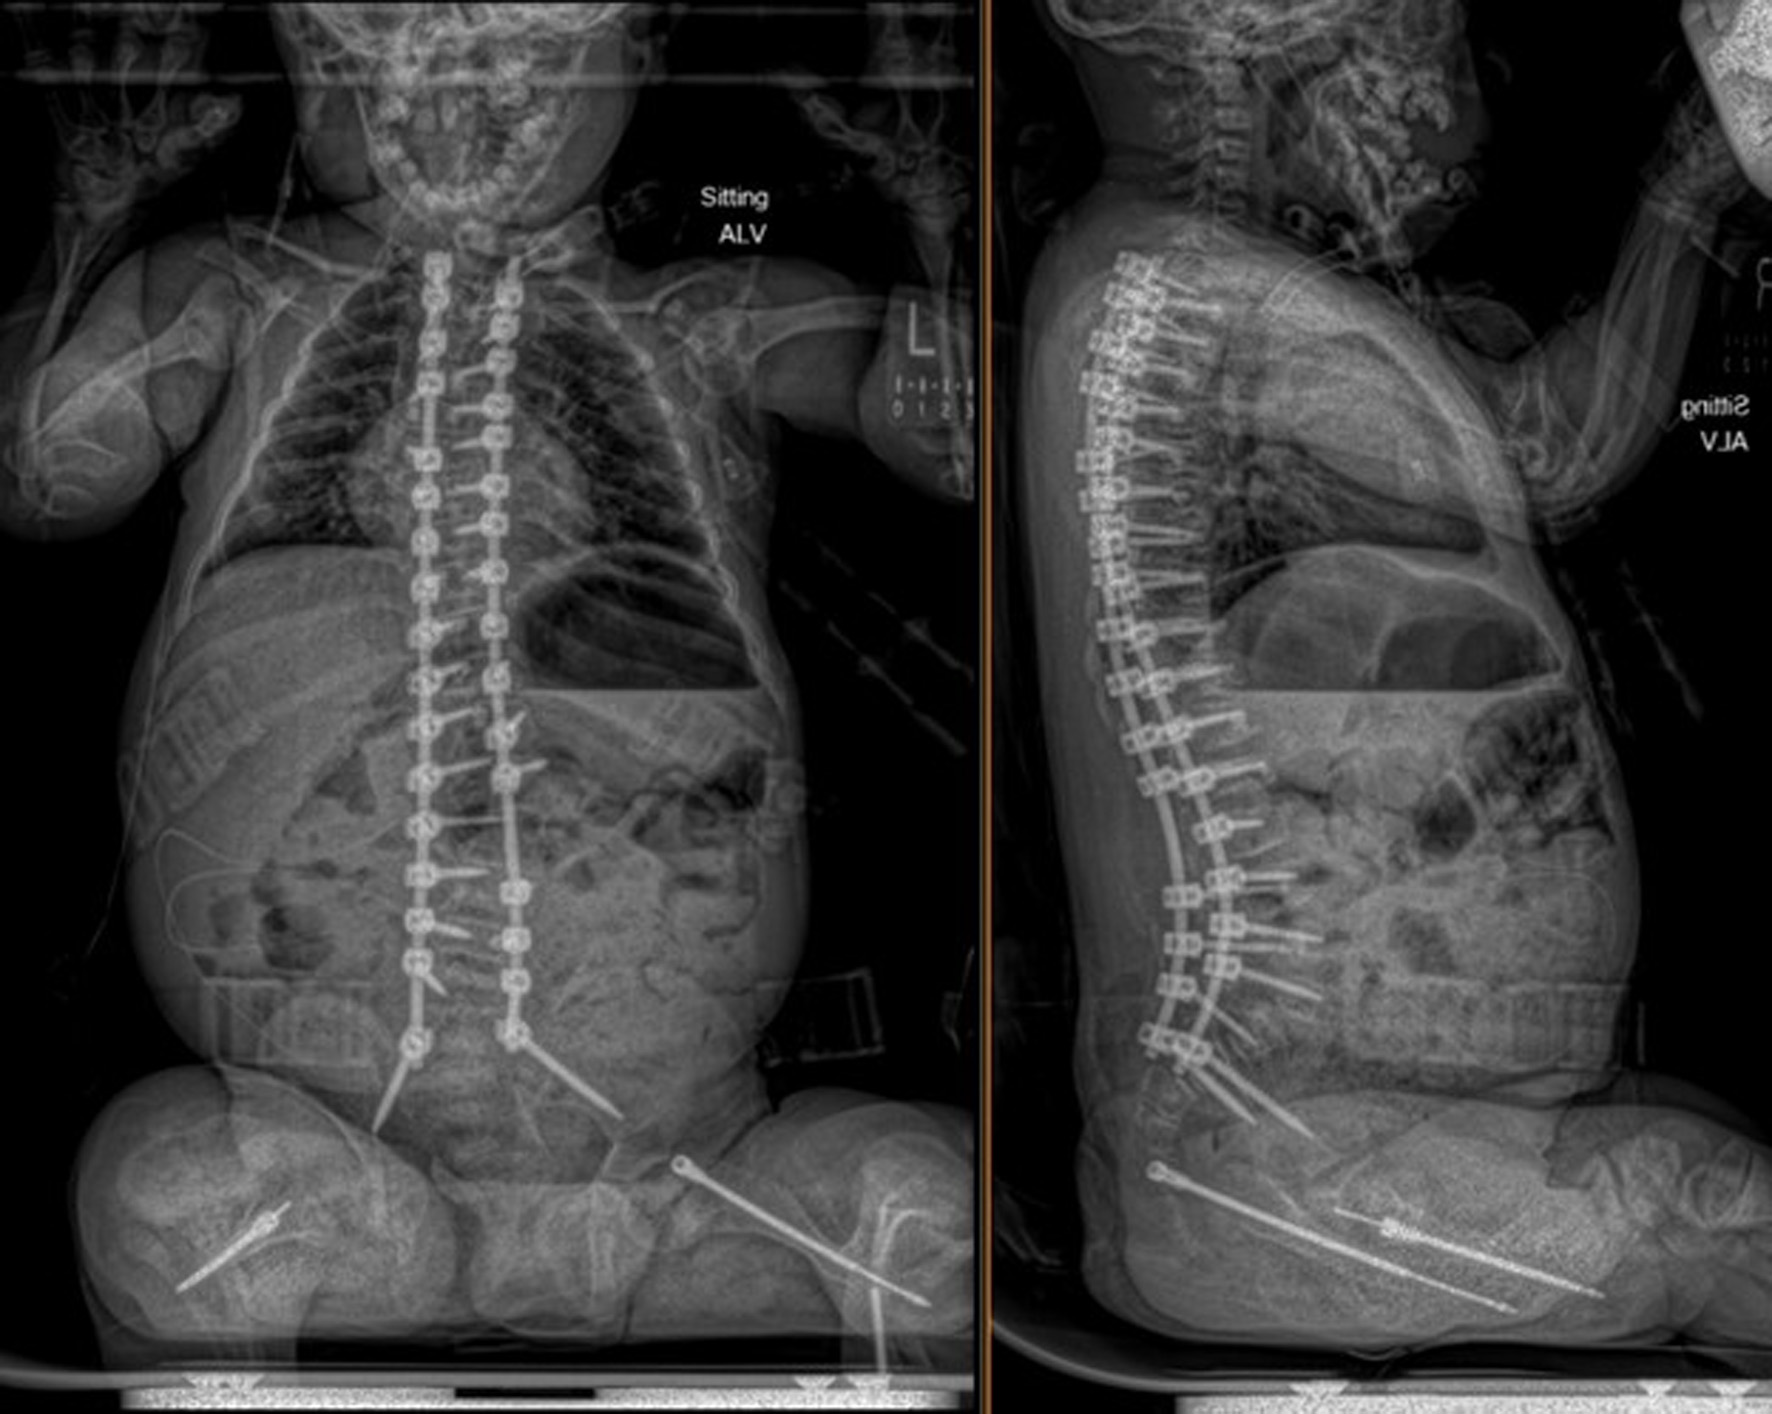

An 11-year-old male, prepubertal child with a diagnosis of OI type II and severe scoliosis presented for T2-pelvis posterior spinal instrumented fusion with posterior column osteotomies and cement vertebral screw augmentation. Preoperative evaluation revealed a 71° thoracic curve and an 85° lumbar curve (Figs 1 and 2). Despite the rarity of survival of a patient with OI type II to this age, the diagnosis was based on DNA testing which documented that the patient was heterozygous for a COL1A1 pathogenic mutation. This mutation converts a highly conserved glycine at amino acid #302 to valine. These mutations have been seen in OI types 1–4. Based on this and the clinical findings at birth, the medical geneticist specialist opined that the patient’s presentation was consistent with OI type II and that no further genetic evaluation was needed. Additional complex past medical history included Chiari I malformation, hydrocephalus status post ventriculoperitoneal (VP) shunt, restrictive lung disease, and chronic tracheostomy with ventilator dependence. The patient also had bowel and bladder incontinence, and a history of multiple long-bone fractures requiring prior orthopedic interventions, including bilateral tibial and femoral osteotomies. Growth parameters were significantly low with a weight of 15.8 kg and height of 90 cm, both below the first percentile for age. The diagnosis of OI was first suspected prenatally when a 20-week ultrasound revealed skeletal anomalies. Delivery was at term via scheduled cesarean section to a 30-year-old mother (G2P1). At birth, the neonate required oxygen supplementation and stimulation for resuscitation, with Apgar scores of 1, 4, and 8 at 1, 5, and 10 min, respectively. Early postnatal imaging showed multiple rib fractures, bowing of long bones, and deformities of the clavicle and femur, consistent with severe OI. Genetic analysis subsequently confirmed the diagnosis of OI type II, identifying a heterozygous COL1A1 pathogenic mutation (c.905G>T) resulting in substitution of glycine with valine at position 302—a mutation known to cause OI types I–IV. Following birth, the infant exhibited respiratory failure due to pulmonary hypoplasia and multiple rib fractures, leading to early ventilator dependence. At 4 months of age, a tracheostomy was performed due to progressive and continued respiratory failure and chronic ventilator dependence. Subsequently, hydrocephalus and Chiari I malformation were identified on magnetic resonance imaging that required placement of a VP shunt. The past surgical history revealed multiple surgical interventions to treat the multisystem effects of OI. These included placement of a feeding gastrostomy, circumcision, tracheostomy, and VP shunt. Orthopedic management involved bilateral tibial osteoplasties with intramedullary rodding and a left tibia and fibula osteotomy with fixation. All previous surgeries were performed under general anesthesia without complications. Current medications included nebulized albuterol every 6 h as needed; cetirizine 10 mg once a day as needed for allergy symptoms; nebulized sodium chloride 0.9% every 4 h as needed for secretion management; calcium carbonate suspension (500 mg (twice a day). Additionally, to promote bone health, a bisphosphonate infusion (zoledronic acid 0.05 mg/kg) was provided every 12 weeks. The bowel regimen included polyethylene oral powder via the gastrostomy tube, enteral sennosides, and glycerin or bisacodyl suppositories as needed. Management of chronic pain included alternating doses of acetaminophen and ibuprofen as needed. Current allergies included pork-derived products, adhesive tape, and environmental allergens. Nutrition was maintained with Boost Kid Essentials oral supplement. Pre-anesthetic physical examination revealed a young child who was tracheostomy and ventilator dependent. Ventilator support was provided by a Trilogy home ventilator. Settings include peak inspiratory pressure 24 cm H2O, positive end expiratory pressure (PEEP) 8 cm H2O, pressure support 16 cm H2O, rate 10 breaths/min with oxygen 0.5–1 L/min as needed to maintain the oxygen saturation. Breath sounds were clear. The cardiovascular examination was unremarkable with a heart rate of 100–110 beats/min. A blood pressure was not obtained due to bone fragility concerns. Preoperative complete blood count and coagulation profile were within normal limits. Additional preoperative laboratory values revealed serum calcium 7.4 mg/dL (normal 8–10 mg/dL), phosphorous 3.8 mg/dL (normal 3.7–5.6 mg/dL), and alkaline phosphatase 115 U/L (normal 137–424 U/L). Preoperative echocardiogram revealed mild pulmonary regurgitation and a patent foramen ovale. Given his severe OI and associated comorbidities, anesthetic planning emphasized fracture prevention during positioning, maintenance of normothermia, careful airway and ventilatory management through the tracheostomy, and readiness for significant blood loss. The patient was assigned an American Society of Anesthesiologists’ (ASA) physical classification IV due to severe systemic disease and ventilator dependence. Multidisciplinary coordination between anesthesiology, orthopedic surgery, pulmonology, and critical care teams was arranged, with plans for postoperative pediatric intensive care unit (PICU) admission for ventilatory and hemodynamic support and monitoring. Pre-medication included aprepitant to prevent postoperative nausea and vomiting as well as gabapentin as part of our usual postoperative pain management regimen. The patient was held nil per os after midnight and transported to the operating room where routine ASA monitors were placed. Anesthesia was induced by the inhalation of incremental concentrations sevoflurane in 50% oxygen and nitrous oxide through the existing tracheostomy. After the induction of anesthesia, two peripheral intravenous cannulas were placed (18 and 18 gauge) with a loosely placed tourniquet to facility identification of the veins. A left ulnar arterial cannula was placed with ultrasound guidance following a negative Allen’s test. A urinary catheter with a core temperature probe was inserted. Maintenance anesthesia included our routine practice to facilitate intraoperative neurophysiologic monitoring. This included total intravenous anesthesia with propofol (50–150 µg/kg/min) and remimazolam (5–10 µg/kg/min) titrated to maintain the bispectral index at 50–60, methadone (0.15 mg/kg) and remifentanil (0.1–0.3 µg/kg/min) adjusted according to the mean arterial pressure (MAP), and lidocaine (1 mg/kg/h). Intraoperative mechanical ventilation was provided by a pressure-regulated, volume-guaranteed mode with a tidal volume of 8 mL/kg and PEEP 5 cm H2O. The rate was adjusted to maintain the ETCO2 between 35 and 40 mm Hg and the FiO2 was adjusted to maintain the oxygen saturation greater than 95%. Prophylaxis against surgical site infection included cefazolin 50 mg/kg every 3 h and a single dose of gentamicin (5 mg/kg). Limitation of the needed for allogeneic transfusions included maintenance of the MAP at 55–65 mm Hg, intraoperative cell saver, a single dose of desmopressin (0.15 units/kg), desmopressin (0.15 µg/kg), and tranexamic acid infusion (50 mg/kg followed by an intraoperative infusion at 5 mg/kg/h). After instrumentation, the MAP was increased as needed by a phenylephrine infusion (0.5–1 µg/kg/min). Intraoperative temperature was managed using a forced air warming device. Prone positioning was performed cautiously and carefully, with meticulous attention to protecting pressure points, securing the airway and maintaining spinal alignment throughout positioning. The patient’s existing right frontal VP shunt was identified and protected throughout positioning. Intraoperative fluids included Normosol-R (850 mL), 5% albumin (250 mL), and a unit of packed red blood cells (320 mL). Urine output was 520 mL with an estimated blood loss of 600 mL. The surgical procedure included posterior spinal fusion with instrumentation from T2 to the pelvis with cemented vertebral screw augmentation (n = 22) from T2–L1 on the right and at T2, T4, T5, T7–11, and L3–4 on the left with posterior column osteotomies from L11–T2. After completion of the 11-h surgical procedure, the patient was turned supine, and ventilation was maintained through the tracheostomy with a patent, unobstructed airway. The cardiovascular status remained stable. The patient was awake, responsive, and followed commands. There were no complaints of pain or nausea. The patient was transported directly from the operating room to the PICU with the anesthesia team in attendance. Postoperative pain was managed with intermittent acetaminophen, a lidocaine infusion, and morphine delivered by nurse-controlled analgesia, which was subsequently transitioned to oral acetaminophen, ibuprofen, valium, and oxycodone managed under the guidance of the pain service. Physical and occupational therapy were involved throughout the hospital stay. Postoperative imaging showed well-aligned spinal instrumentation without concerns (Fig. 3). Routine home medications were restarted. The remainder of the postoperative course was uneventful, and he was discharged home on postoperative day 5. Follow-up at 3 months postoperatively with radiographic imaging demonstrated overall appropriate alignment and positioning of all hardware.

Figure 3. Postoperative seated radiographs following scoliosis correction with T2 to pelvis posterior spinal instrumented fusion, posterior column osteotomies, and cement vertebral screw augmentation.